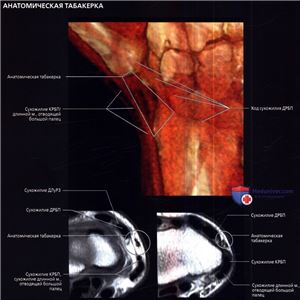

При трехмерной КТ реконструкции с наложением мягких тканей показаны границы анатомической табакерки: длинный разгибатель большого пальца (III канал), пересекает запястье с медиальной стороны к латеральной над сухожилиями короткого и длинного лучевых разгибателей запястья (II канал), образуя заднюю границу, тогда как сухожилия длинной мышцы, отводящей большой палец и короткого разгибателя большого пальца (I канал) образуют переднюю границу. Через анатомическую табакерку проходят лучевой нерв и его поверхностная ветвь, а также одноименные артерия и вена. На МР-томограмме анатомическая табакерка показана в аксиальной проекции.

При трехмерной КТ-реконструкции с наложением мягких тканей показан мышечно-сухожильный перекрест короткого разгибателя большого пальца и длинной мышцы, отводящей большой палец, с сухожилиями длинного и короткого лучевых разгибателей запястья, продолжающийся в дистально-латеральном направлении непосредственно проксимальнее удерживателя разгибателей. На аксиальных МР-томограммах их сложное взаимное расположение показано на поперечном срезе. На нижней правой МР-томограмме показан дистальный отдел предплечья: короткий разгибатель большого пальца и длинная мышца, отводящая большой палец, лежат кнаружи и немного кзади от сухожилий короткого и длинного лучевых разгибателей запястья. На нижней левой и верхней правой МРТ короткий разгибатель большого пальца и длинная мышца, отводящая большой палец, пересекают сверху длинный и короткий лучевые разгибатели запястья и располагаются на латеральной поверхности лучевой кости. На верхней левой МР-томограмме—наиболее дистальном из этих срезов, на уровне бугорка Листера, перекрест заканчивается, и сухожилия занимают свое положение на запястье.